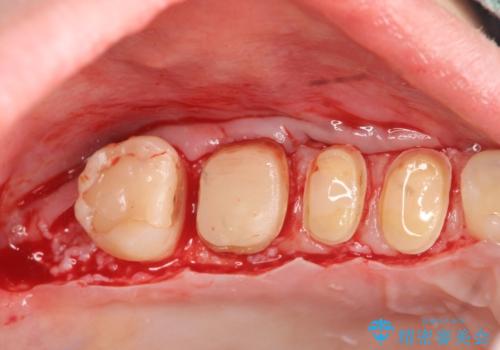

歯周外科を行い歯ぐきの整備を行うセラミック治療

銀歯周囲の虫歯再発や、歯ぐきよりも深い虫歯、根尖性歯周炎と言った複合的な問題を、

歯周外科、精密根管治療、セラミック治療を行い、妥協のないセラミック治療を計画します。

今回の治療では歯ぐきの問題を解決するため、歯周外科を行いました。